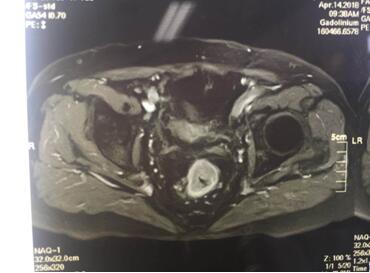

入院后譚曙光主任帶領賀賽奇副主任、周高副主任醫(yī)師及周平主治醫(yī)師等科室業(yè)務骨干為汪老制定詳細診療計劃。術前盆腔MRI及腸鏡、病理診斷考慮低位直腸腺癌(T3aN0M0)。鑒于汪老年老體弱,病變位置低,基礎疾病多,耐受力較差,譚主任及其手術團隊精益求精,不斷完善診療措施,術前采取MDT(多學科合作)模式,于4月18日在全麻腹腔鏡下行直腸癌根治術+D3淋巴結清掃術+粘連松解,手術順利,術中徹底松解腹腔內粘連,標準的TME(直腸全系膜切除)及D3淋巴結清掃,腹腔鏡下吻合口加固縫合,手術出血僅30ml,在原有的手術切口處取出手術標本。